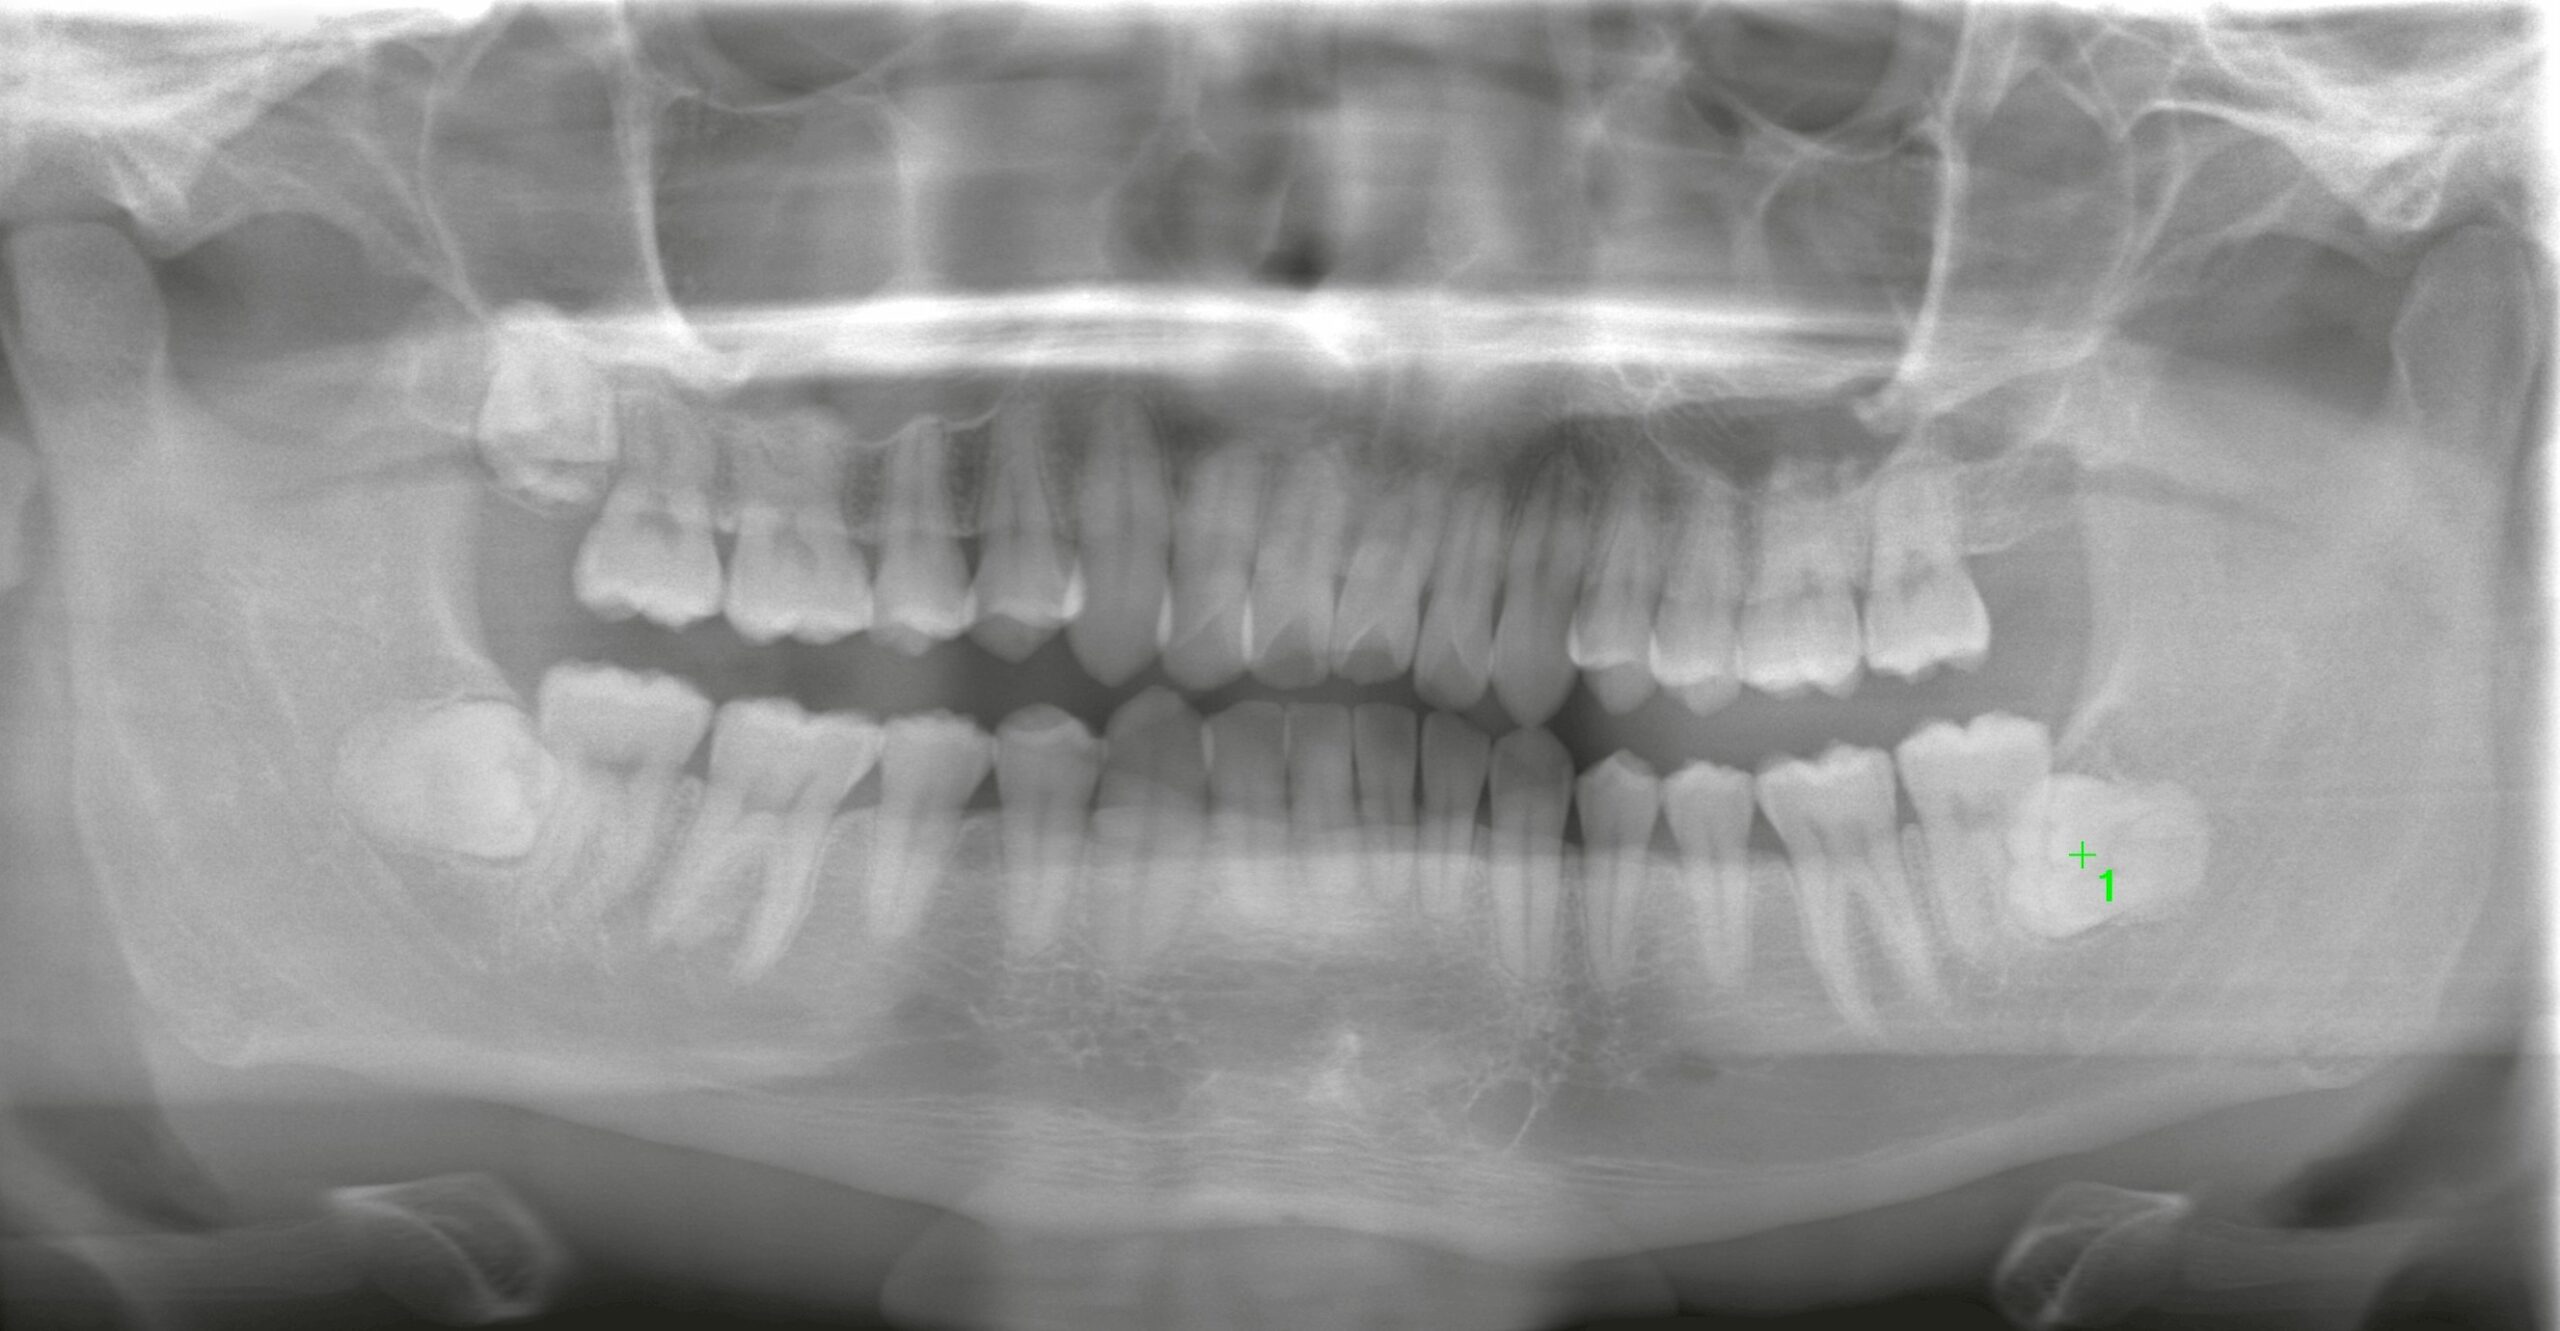

左右上下すべての親知らずが完全埋伏しているケースでした。

特に問題となったのは下顎です。

パノラマX線写真では、歯根が深い位置に存在し、下歯槽神経に近接していることが示唆されました。

そこでCT撮影を実施。

CT精査の結果、

・歯冠及び歯根は完全に骨内に埋伏

・根尖部は下歯槽神経管に極めて近接

・歯根は長く、やや肥大傾向

・隣在歯の歯根とも近接

という、複数の難易度因子を併せ持つ状態でした。